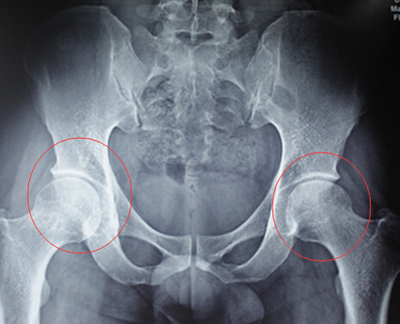

股骨头缺血性坏死是由于多种原因导致的股骨头局部血运不良,…… 【详情】

股骨头缺血性坏死患者去医院看病时,对于医生建议做X线、CT或…… 【详情】